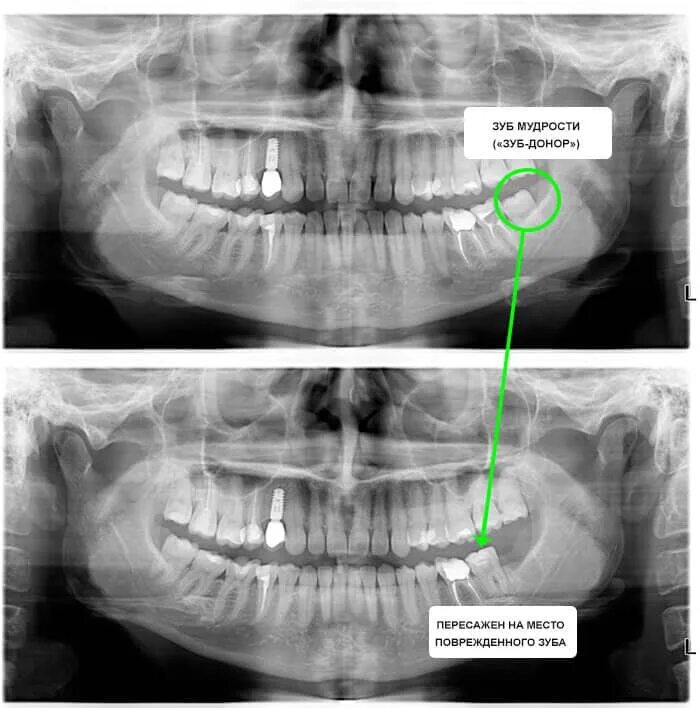

Зубы в 38 лет